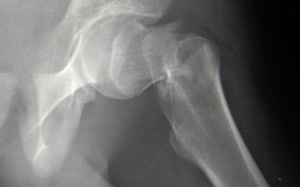

Một nghiên cứu mới của các nhà khoa học Tây Ban Nha và Thổ Nhĩ Kỳ cho thấy collagen trong da gà có thể giúp phòng ngừa các triệu chứng của bệnh xương khớp.